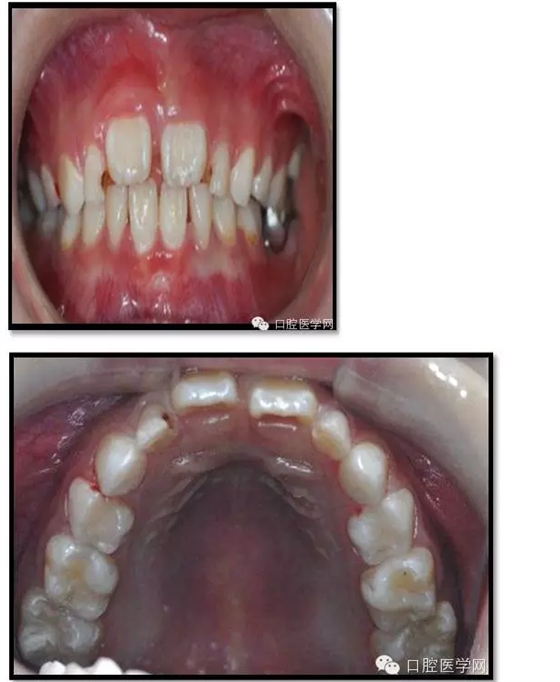

治療結(jié)束后3個(gè)月復(fù)查

復(fù)查:無不適

檢查:口腔衛(wèi)生一般,牙面軟垢菌斑中量。 85O、84DO充填完好,邊緣密合,叩(-),不松,齦無紅腫。

75帶環(huán)絲圈式間隙保持器完好,無松動(dòng),無咬合不適。

余牙充填體完好密合,未查及繼發(fā)齲和新發(fā)齲壞。

治療結(jié)束后7個(gè)月復(fù)查

85O、84DO充填完好,邊緣密合,叩(-),不松,齦無紅腫。X線:84、85根分歧透射影,44、45骨硬板連續(xù),恒牙胚上方骨板厚約2-3mm。75帶環(huán)絲圈式間隙保持器完好,無松動(dòng),無咬合不適。64MO中齲。 64MO中齲去腐凈,自酸蝕,SEBOND,樹脂充填。 口腔衛(wèi)生宣教,囑3個(gè)月后復(fù)診。